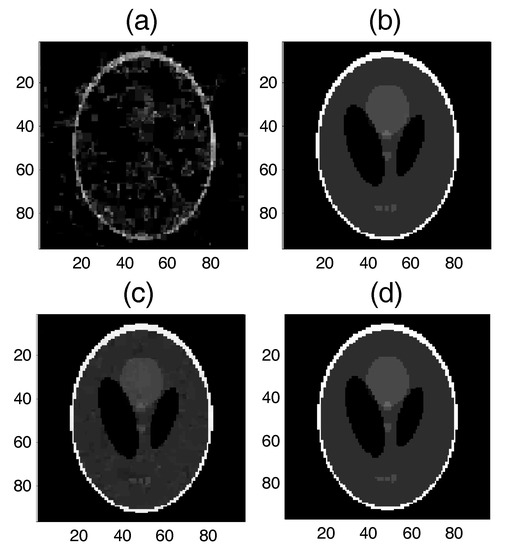

5.2.2. Test 2 for Real-World Data (2D MRI)